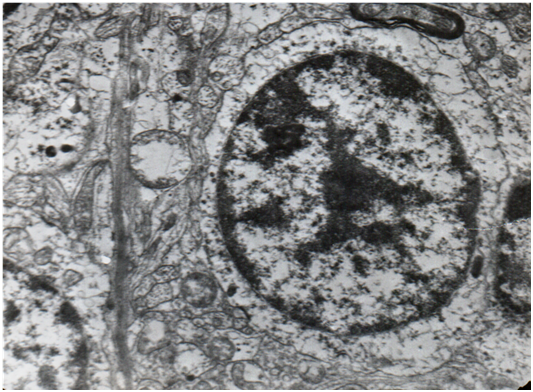

The granular layer consists of the granular cells, the Golgi type II neurons, the microglial cells of Hortega, the terminals of the mossy fibers, the myelinated recurrent collaterals of Purkinje cells and the astroglial sheaths (Figure 2). The granular cells are characterized by a big nucleus which contains heterochromatin attached to the nuclear membrane, nucleolus, euchromatin, smooth endoplasmatic reticulum, small spheroid mitochondria and (mainly) unattached ribosomes. The axons of the granular cells are divided, forming the parallel fibers which are contacted by the dendrites of the Purkinje cells. The microglial cells of Hortega consist of a dark oblong nucleus and dark perikaryum with small mitochondria, many free ribosomes and cisternae of the smooth endoplasmatic reticulum. The Golgi type II neuron is four or five times as big as the granular cell. It consists of a big nucleus (containing mainly euchromatin), nucleolus, small mitochondria, smooth endoplasmatic reticulum, Golgi apparatus, many free ribosomes and lysosomes. Sometimes the endoplasmatic reticulum, the Golgi apparatus and the lysososmes are contacted, producing a formation which was called GERL.10 Cerebellar cortex has its own neuroglia, the neuroepithelial Golgi cell, which makes astroglial sheaths round the dendrites of Purkinje cells. When the Purkinje cells degenerate the neuroepithelial cells become hyperplastic and form the neuroglia of Bergmann. This neuroglia is the evidence of a chronic cerebellar degeneration.

Figure 2Granular cells, a Golgi II cell and myelinated recurrent collaterals from Purkinje cells from the granular layer of the human cerebellum (24.400x).